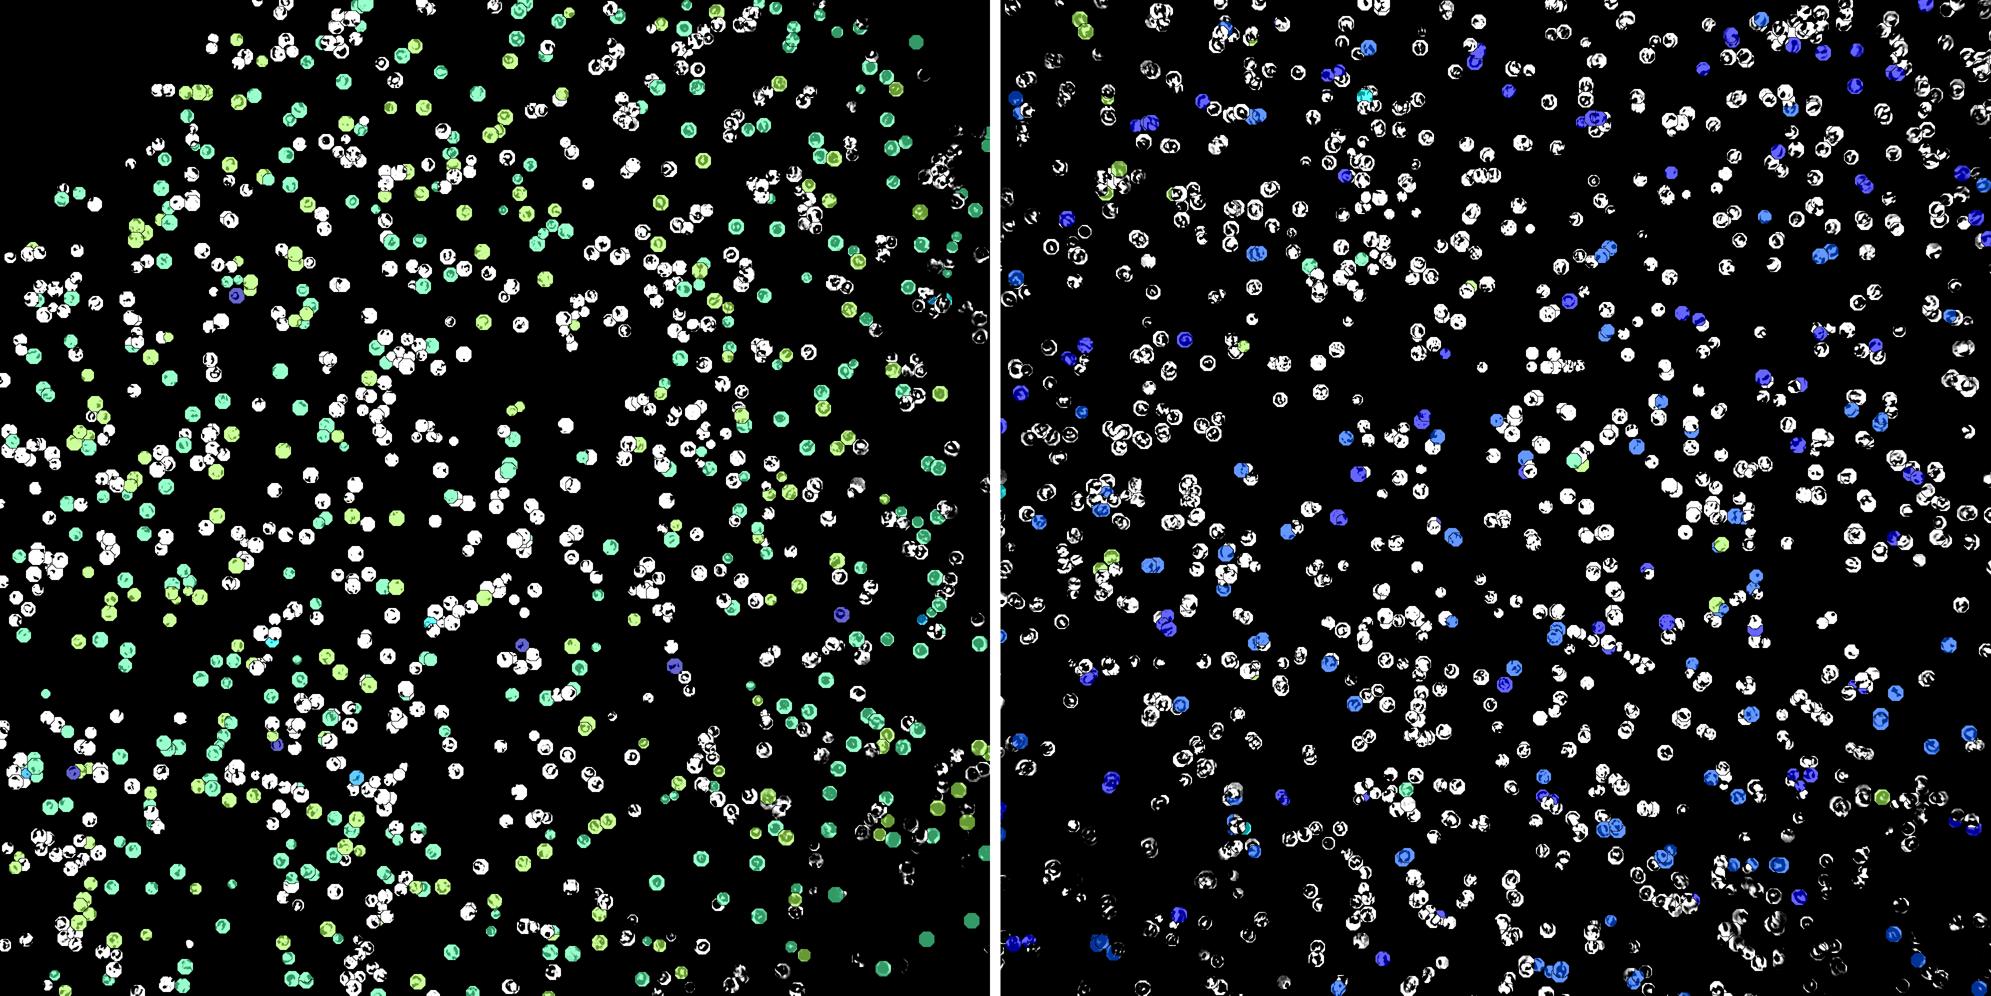

Cells labelled with CD15 CD24

Peripheral blood lymphocytes

Inflammatory Disease

Cell populations before and after treatment